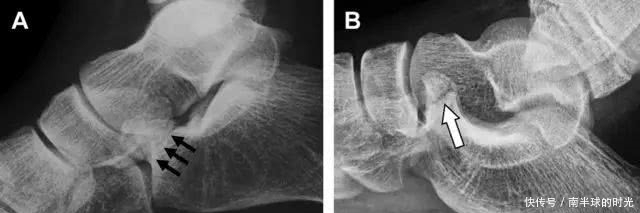

涉及到三角韧带和外侧副韧带(LCL)的复杂性骨折常常不难发现,尤其是存在表面软组织肿胀时。然而,后胫腓韧带牵拉引起的胫骨后踝骨折则很难发现。这些骨折大小不一(图 2),却很重要,因为他们常与胫骨远端螺旋骨折有关,或者是三踝骨折的一部分。

图 2 胫骨后踝骨折。A 侧位片示来源于胫骨后踝的一个小骨折碎片(箭头),因踝部扭伤导致;B 另一位跖屈损伤的患者,侧位片示一个大骨折块(箭头)